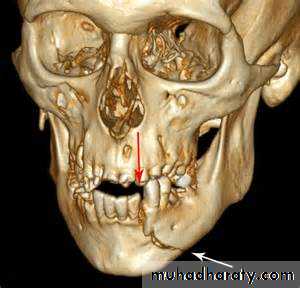

• Planning of fracture repair in complex areas: acetabulum, foot, ankle and wrist.

• Display of complex anatomy for planning of cranial and facial reconstruction surgery